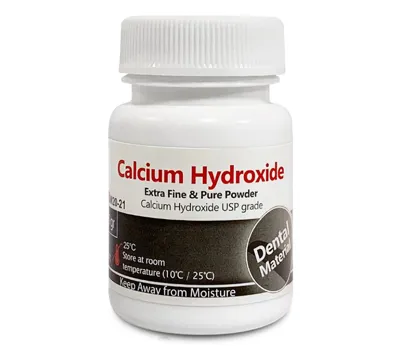

پودر کلسیم هیدروکساید

شرکت/سازنده: MORVABON

کشور سازنده: ایران

برای اطلاع از قیمت محصول با شماره پشتیبان تماس حاصل فرمائید.

پودر کلسیم هیدروکساید

شرکت/سازنده: Golchai

کشور سازنده: ایران

برای اطلاع از قیمت محصول با شماره پشتیبان تماس حاصل فرمائید.